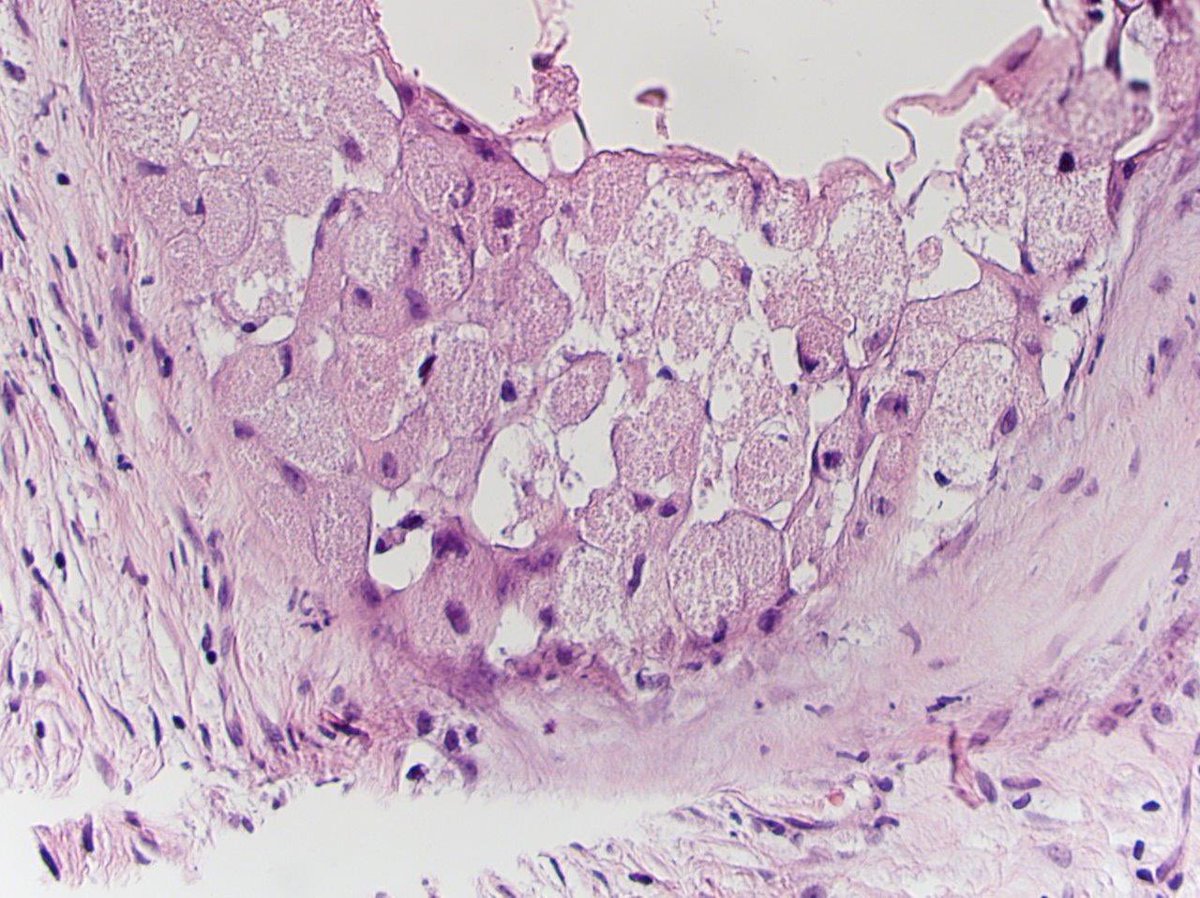

Laryngeal carcinosarcoma (sarcomatoid SCC). Sometimes you have to look v hard to find any evidence of epithelial differentiation. This was the only 1mm focus +ve for p40 and cytokeratins. Don’t believe it’s a sarcoma until you’ve done levels and every CK in your armoury #ENTPath